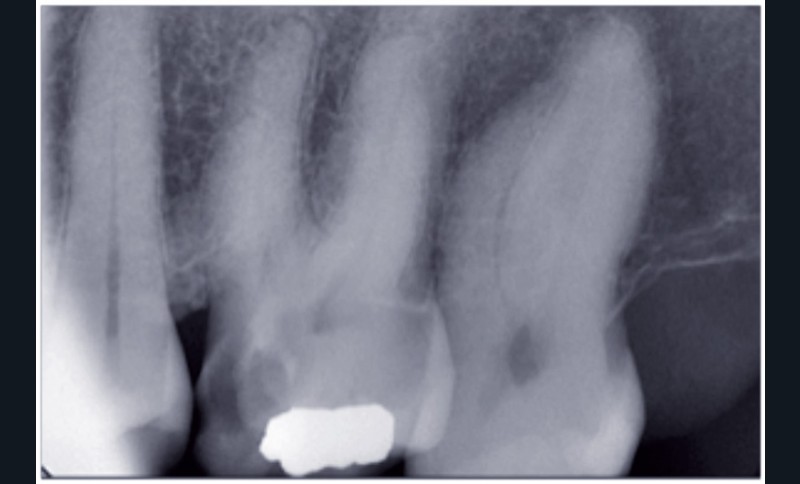

• Deux radiographies rétroalvéolaires sont effectuées

au cours du traitement endodontique : l’acte a pour code HBQK040 et pour libellé « Radiographies intrabuccales rétroalvéolaires sur un secteur de 1 à 3 dents contiguës préinterventionnelle ou perinterventionnelle avec radiographie finale pour acte thérapeutique endodontique ».

Les honoraires forfaitaires sont de 11,97 €.

• Trois radiographies rétroalvéolaires sont effectuées au cours du traitement endodontique : l’acte a pour code HBQK303 et pour libellé « Radiographies intrabuccales rétroalvéolaires sur un secteur de 1 à 3 dents contiguës préinterventionnelle, perinterventionnelle et finale pour acte thérapeutique endodontique ». Les honoraires forfaitaires sont de 15,96 €.

Dans les deux cas de figure, les dates des radiographies n’ont pas d’incidence sur le « tarif forfaitaire ». Ces radiographies peuvent être réalisées dans plusieurs séances (cas de la reprise du traitement endodontique, par exemple). Les honoraires restent ceux fixés forfaitairement.

Les données de la littérature professionnelle, tout comme la recommandation de la HAS (novembre 2008), conseillent de réaliser, au moins, trois radiographies pour un traitement endodontique. Même en utilisant un localisateur d’apex, la radiographie per-opératoire est essentielle pour doubler la mesure électronique par une mesure visuelle, broches en place.

Le « forfait deux radiographies » prévu par la CCAM est donc d’utilisation exceptionnelle.

La plupart du temps, l’acte d’endodontie est associé au « forfait trois radiographies ».